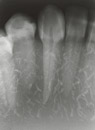

- Jaw model allows the mastering of bisecting techniques

- Jaw model is X-Ray compatible

- Acquire basic X-Ray techniques such as film angle and projection angle for each area